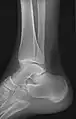

- مچ (قوزک) پا - AP و جانبی

مچ پا قدامی

چرخش داخلی ۱۵ درجه جانبی

جانبی (کمی کم کیفیت با دیدن مستقیم از طریق مفصل مچ پا)

صفحه جانبی مایل (برای تجسم مرز خلفی تیبیا)